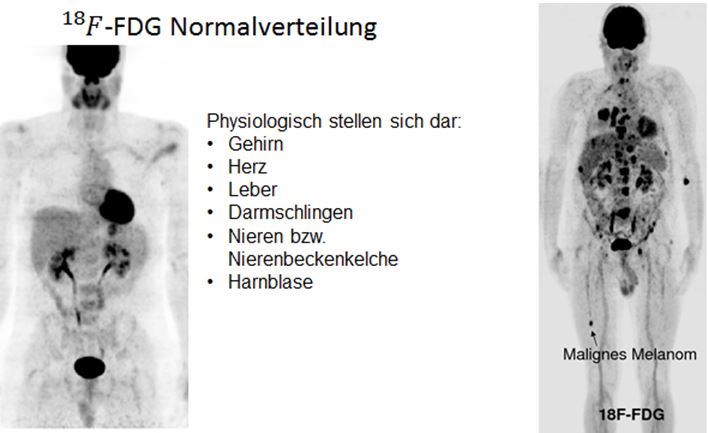

F-18-FDG (F18-Desoxyglukose), ein mit radioaktivem Fluor markiertes Traubenzuckermolekül. ist das weitverbreitetste Radiopharmakon und wird hauptsächlich in der Onkologie eingesetzt. In der Tumordiagnostik mit FDG macht man sich zunutze, dass Krebszellen, deren Wachstum entreguliert ist, einen deutlich erhöhten Traubenzuckerverbrauch gegenüber gesunden Zellen haben. Im späteren PET-Bild hebt sich der Tumor dadurch ganz deutlich vom umliegenden, gesunden Gewebe ab, weil sich das FDG in Tumorzellen anreichert.

8. Welche Tumore und ihre Metastasen werden mit -FDG dargestellt?

- Bronchialkarzinome

- Colon-und Rektumkarzinome

- Oesophagus-und Magenkarzinome

- Pankreaskarzinome

- Hodgkin- und non-Hodgkin-Lymphome

- Mammakarzinome

- Ovarialkarzinome

- Maligne Melanome

- HNO-Tumore

- CUP